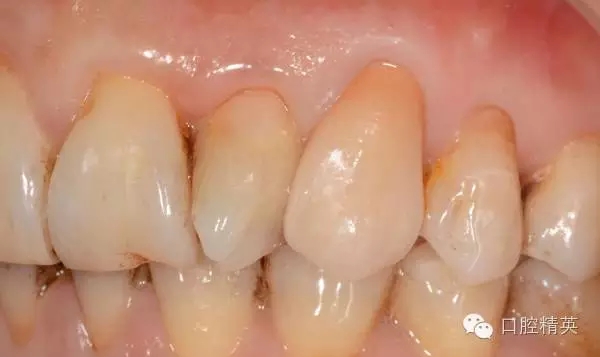

11.12.13頸部楔形缺損,探敏感,牙髓活力正常.

11.12.13 楔形缺損

二. 11.12.13.樹脂修復(fù)